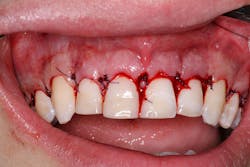

After seeing the great return on investment his brother received from Dr. Glassman’s New York City dental office, one patient seized the opportunity for a consultation of his own. As a healthy 22-year-old college student, the patient sought out dentistry to enhance his facial esthetics and offer his smile a well-deserved promotion (figure 1).

During the initial appointment, the patient stated that his objective was to lessen the amount of gums he displayed while smiling. Records were obtained, including facial photos, intraoral scan, and CBCT. Through quantitative analysis, the height-to-width ratio of his anterior central teeth was nearly 1:1, with the ideal ratio of width to height being 0.80. Also noted was the wear on the teeth. This caused the teeth to be 8 mm in length when they should be between 10 mm and 11 mm.